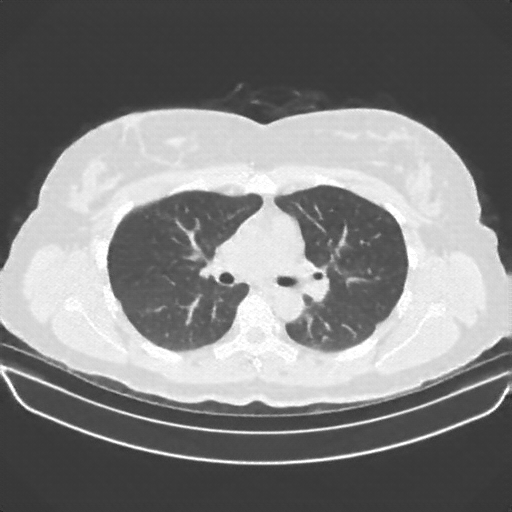

Reconstructed NATIVE CT scan (cycle consistency)

Full window (WL 1023.5, WW 4095 β†’ Low βˆ’1024, High +3071)

Lung window (WL -600, WW 1500 β†’ Low βˆ’1350, High +150)

Mediastinum window (WL 40, WW 400 β†’ Low βˆ’160, High +240)